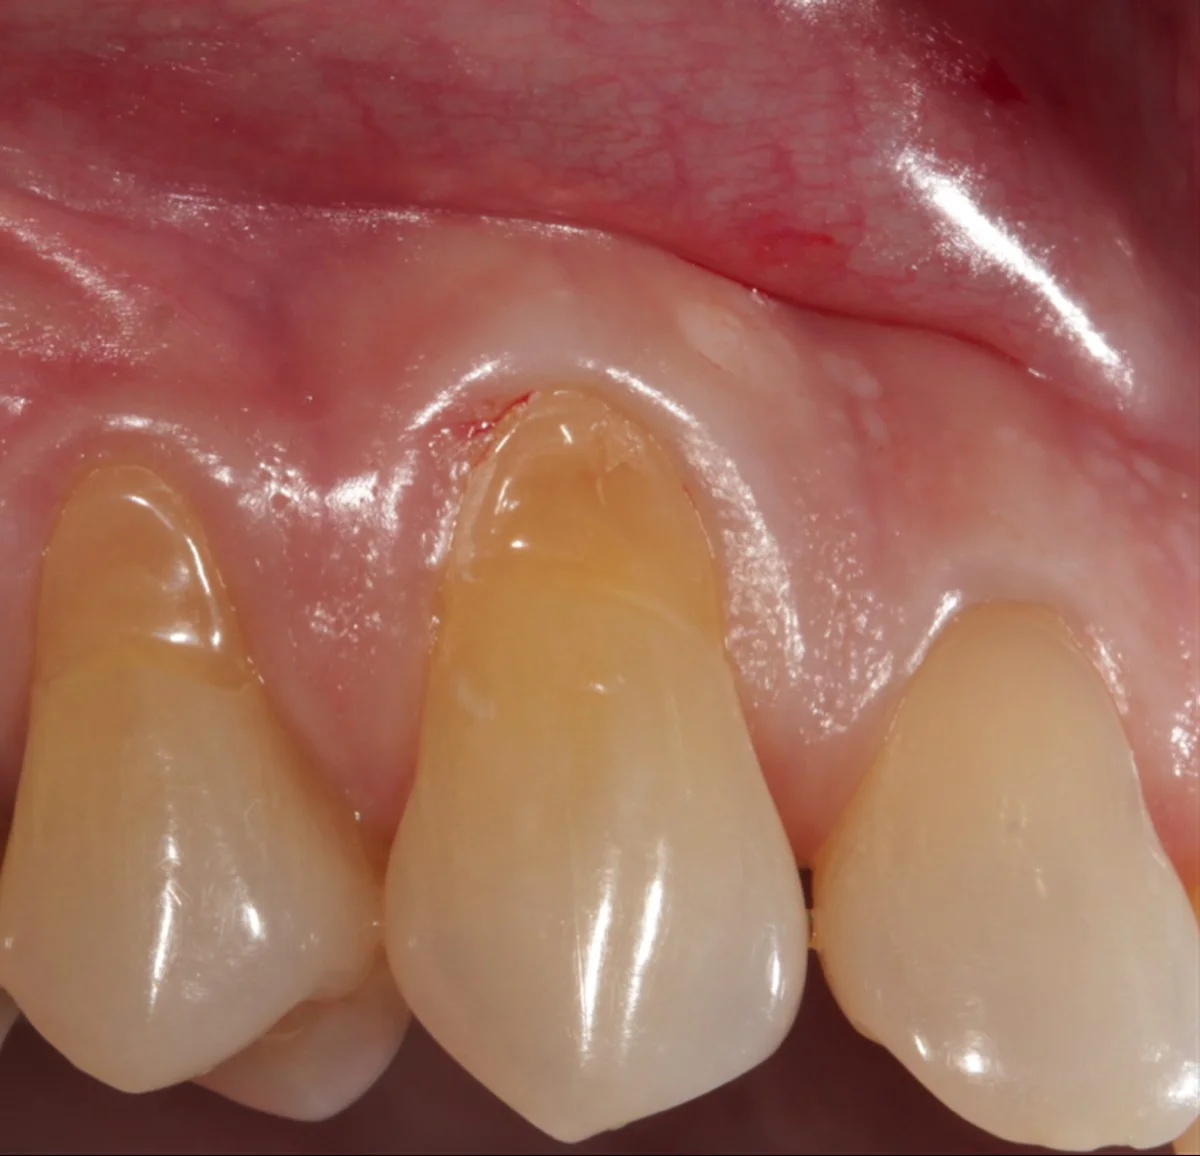

- Zčervenání nebo podráždění dásní — pokud je směs příliš agresivní.

Jděte k zubaři, pokud máte ostrou bolest, krvácení dásní nebo viditelné „leštěné“ skvrny na zubech. V ČR většina zubních ordinací provádí profesionální hygienu a Air-Flow za rozumný poplatek — to je levnější a bezpečnější než riskovat sklovinu.